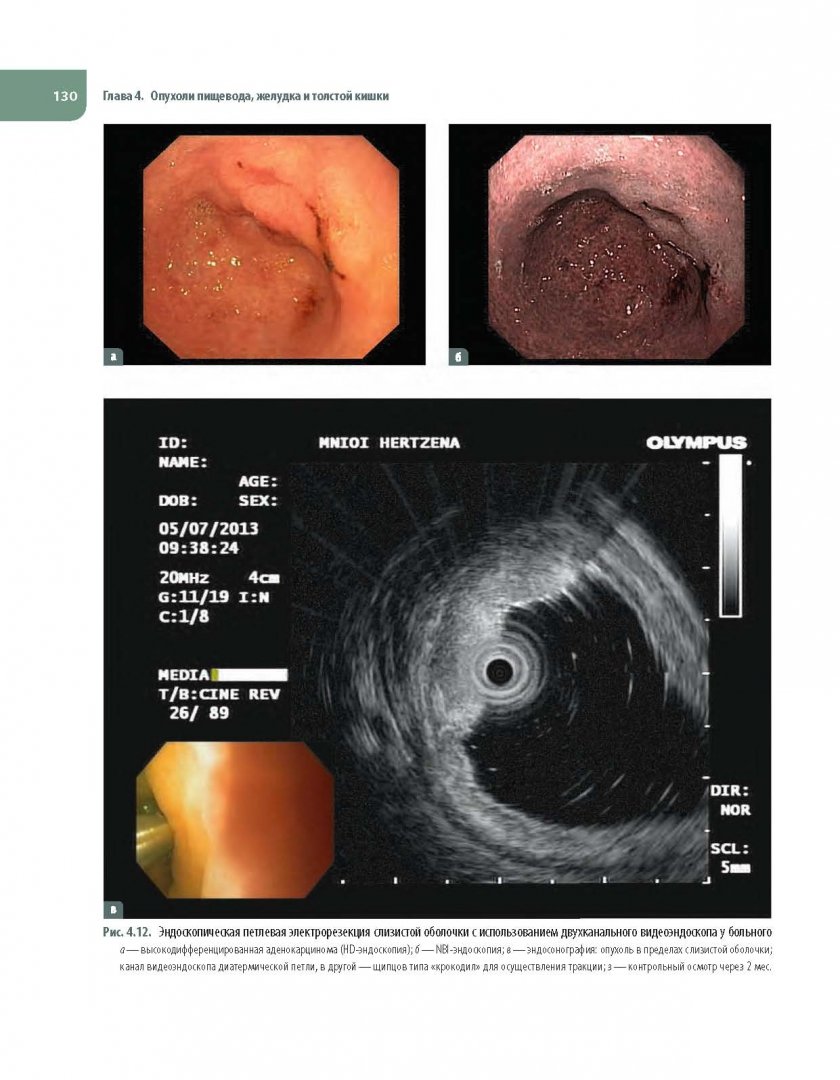

Атлас эндоскопии

Атлас эндоскопии 71 фото